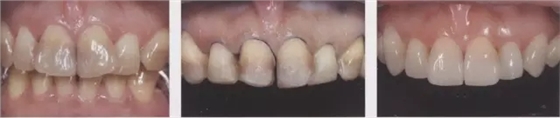

1、嵌體和高嵌體 在磨牙區(qū)域,由于牙齒近中面以及遠中面的傾斜程度不同,常會遇到分離困難的病例。例如,智齒的近中根傾斜,引起鄰牙根間隙過窄的情況。相鄰牙齒的近中傾斜,牙冠進入被處理牙倒凹處的情況(圖2、3)。以上情況,鄰接面由于齲齒形成窩洞,即便是運氣好在齦下做了分離,也會因為出血造成取模困難、頰舌的成形變大。所以采取以下處理措施。 1、術(shù)前拍攝牙片,根據(jù)牙根的傾斜判斷有沒有引起鄰牙根間隙過窄的情況。若沒有傾斜,就是簡單病例。 2、若智齒沒有對合牙,也考慮拔除智齒。 3、鄰接面用樹脂填充之后,用間接法進行烤瓷嵌體或烤瓷高嵌體修復(fù)。 1、貼面治療 對于變色牙齒進行貼面治療的情況下,牙頸部觀察無變色的情況下,可直接在齦上做成形。普通成形深度能夠保存牙釉質(zhì),因而判斷為簡單病例。(圖4) 如果牙頸出現(xiàn)變色,就需要進行齦下成形,難度增加。如果也存在前突問題,為改善變色貼面不能做厚,因而難度會更高。如果希望糾正前突、改善變色,則需要增加切削量,甚至可能進行拔髓。另外,由于粘接對象主要是牙本質(zhì),因而需要格外注意。

圖4牙頸部無變色病例。雖然變色很嚴重但由于未延伸到牙頸部(左圖),可進行齦上成形(中),最終調(diào)整到了很自然的顏色。(右)

圖5牙頸部變色的病例。貼面發(fā)生脫離,并有前突(上圖)。去除貼面后,整體變色明顯,因而進行齦下成形,并做了1mm以上的切削。左1要進行拔髓(下左)。由于粘結(jié)對象大部分為牙本質(zhì),取模前先進行牙本質(zhì)染色,后做全瓷貼面試戴(下右)。